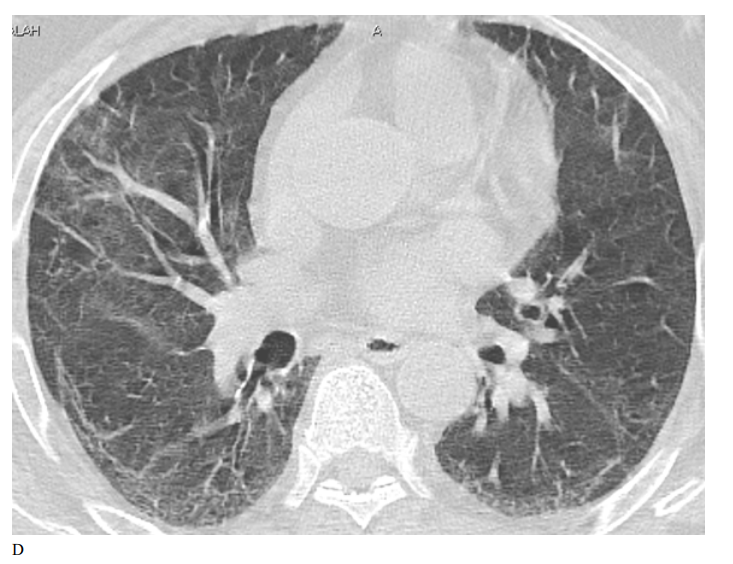

Figure 2: Male patient in remdesivir group shows bilateral ground glass opacities affecting mainly upper lobes and pleural based with small areas of atelectatic bands, Covid severity score 18, while figure D 3 months after treatment shows marked improvement of already present infiltrates with Covid severity score 8.